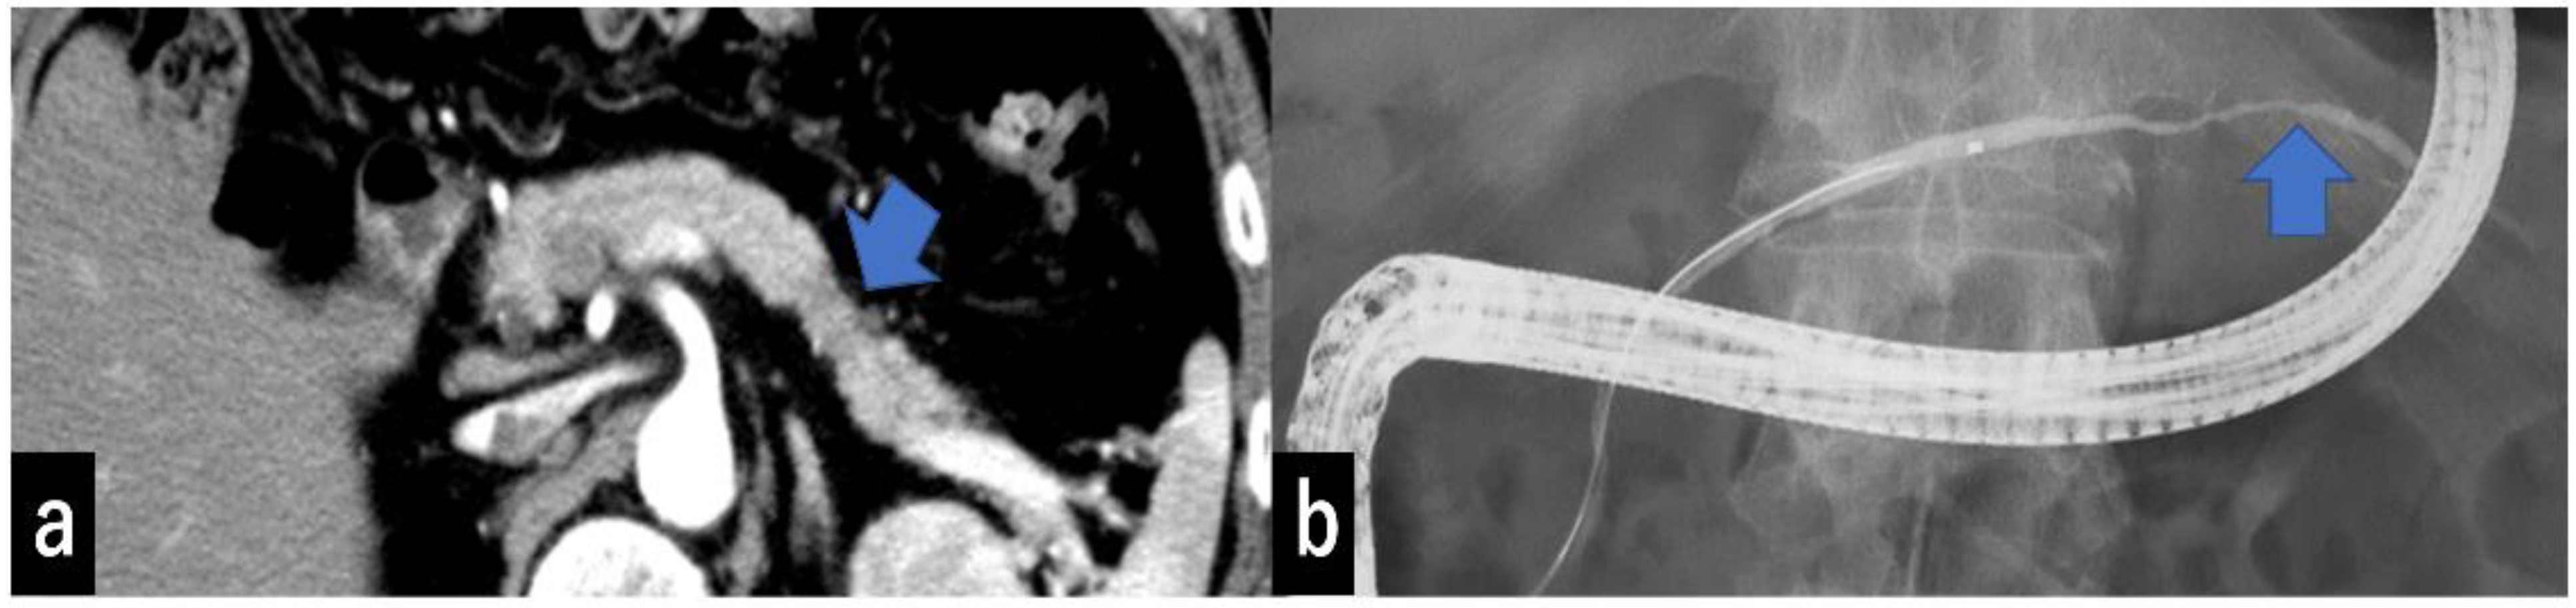

- Kobashi, Y.; Uchiyama, M.; Matsui, J. The “K-Sign”-A Nove CT Finding Suggestive before the Appearance of Pancreatic cancer. Cancers 2021, 13, 4222. [Google Scholar] [CrossRef] [PubMed]